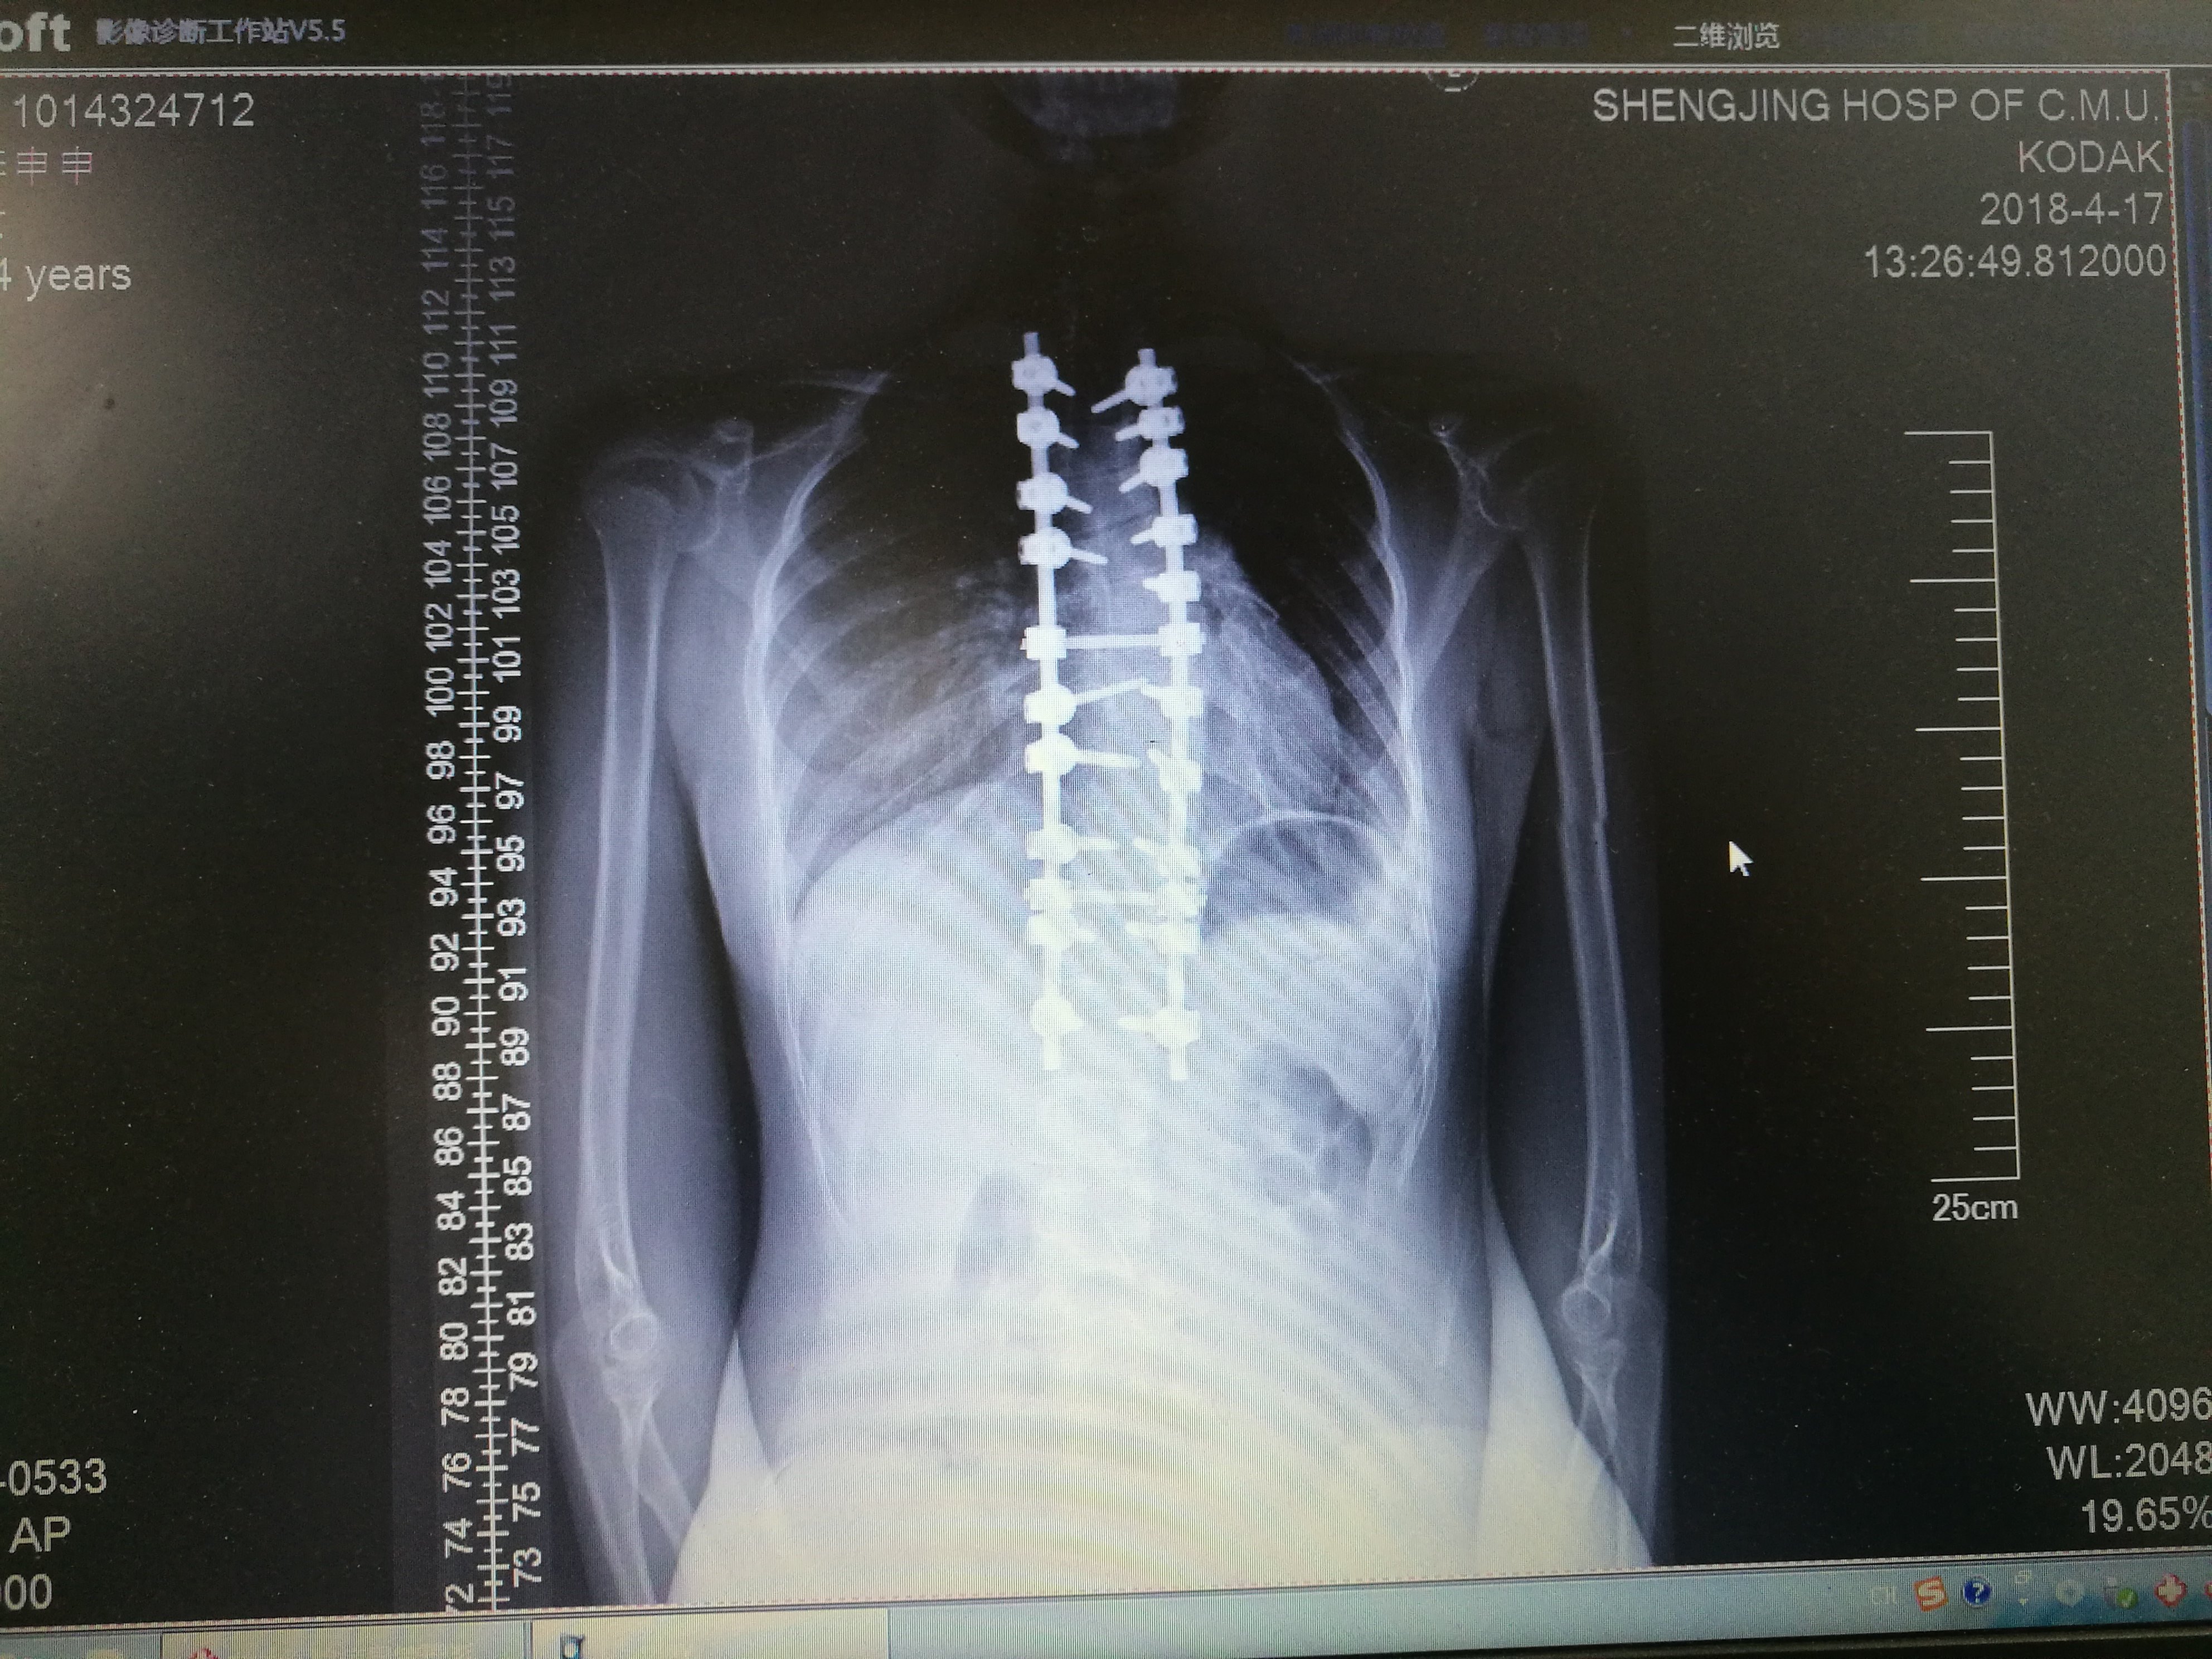

脊柱侧弯 术中影像

脊柱侧弯手术

患者:男,11岁,先天性脊柱侧弯----腰终于挺直了.

【案例】胸腔镜下微创脊柱侧弯矫形术

特发性脊柱侧弯生长棒术后脱钩